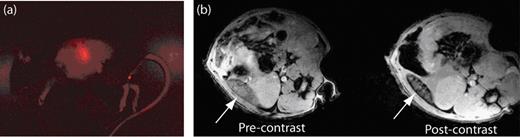

A promising new direction for SPIO is their use in tracking the migration and biodistribution of cells in vivo (Figure 3 ). The ability to track cells is expected to have a significant impact in many clinical applications, including circulating cell–based therapies. Cell tracking typically involves labeling cells ex vivo and subsequently implanting or systemically administering them into living subjects. It has been well documented that many cell types can be labeled by simple incubation with SPIO including monocytes and macrophages.19,20 SPIO can be internalized by phagocytosis, receptor-mediated endocytosis, or fluid phase–mediated endocytosis. Labeling efficiency is dependent on both SPIO size and surface coating. In general, it has been found that the larger SSPIO nanoparticles and charged surface coatings (anionic or cationic) are preferable to the smaller USPIO particles and neutral surface coatings (eg, dextran), respectively.19,21

Fluorescent and magnetic resonance (MR) images revealing the biodistribution of B cells in mice. (a) Fluorescent image of a mouse that has been injected with B cells that have been labeled with ultrasmall superparamagnetic iron oxide (USPIO) and the fluorescent dye CellVue® NIR815. The fluorescent image clearly shows the localization of B cells within the spleen. (b) MR images of the spleen (white arrow) before and after the injection of the USPIO-loaded B cells. The migration of USPIO-loaded B cells to the spleen results in a loss in signal intensity on T2-weighted images.